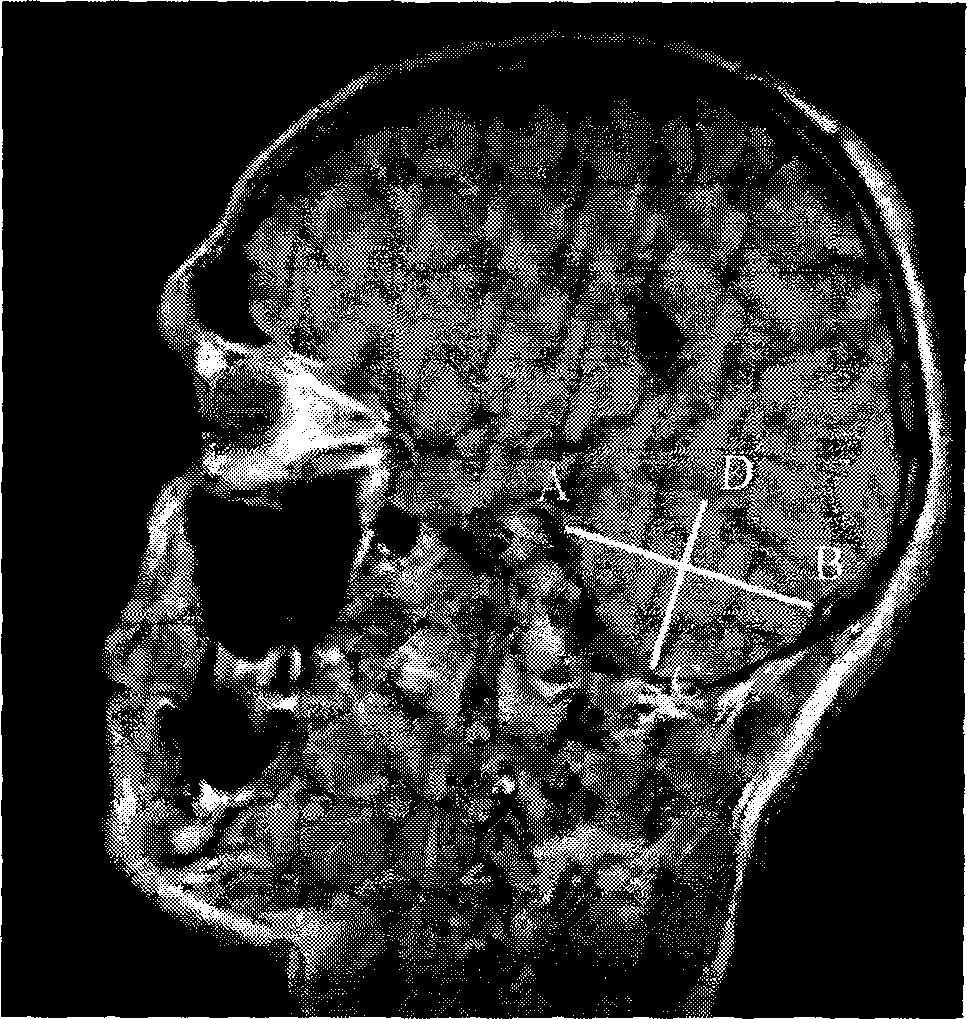

Т1-ВИ в сагиттальной плоскости (второй парасагиттальный срез):

AB – длина полушария мозжечка; CD – высота полушария мозжечка

Было установлено, что ширина полушарий мозжечка у юношей превышает соответствующий показатель у девушек и составляет 105,6±0,9 мм против 100,4±2,2 мм. Рассмотрены показатели ширины каждого полушария отдельно: ширина левого полушария у юношей составила 47,6±0,7 мм, у девушек — 42,9±0,5 мм; ширина правого полушария — 48,4±0,8 мм у юношей и 43,6±0,7 мм у девушек (см. рис. 1).

Что касается длины полушарий, достоверные гендерные различия были выявлены только для левого полушария, длина которого у девушек превышает соответствующий показатель у юношей (60,0±1,4 мм против 58,0±0,7 мм).